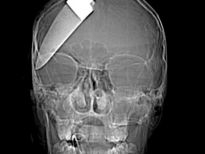

Şoke eden röntgen filmleri

Bu röntgen filmleri görenleri şaşkına çeviriyor!